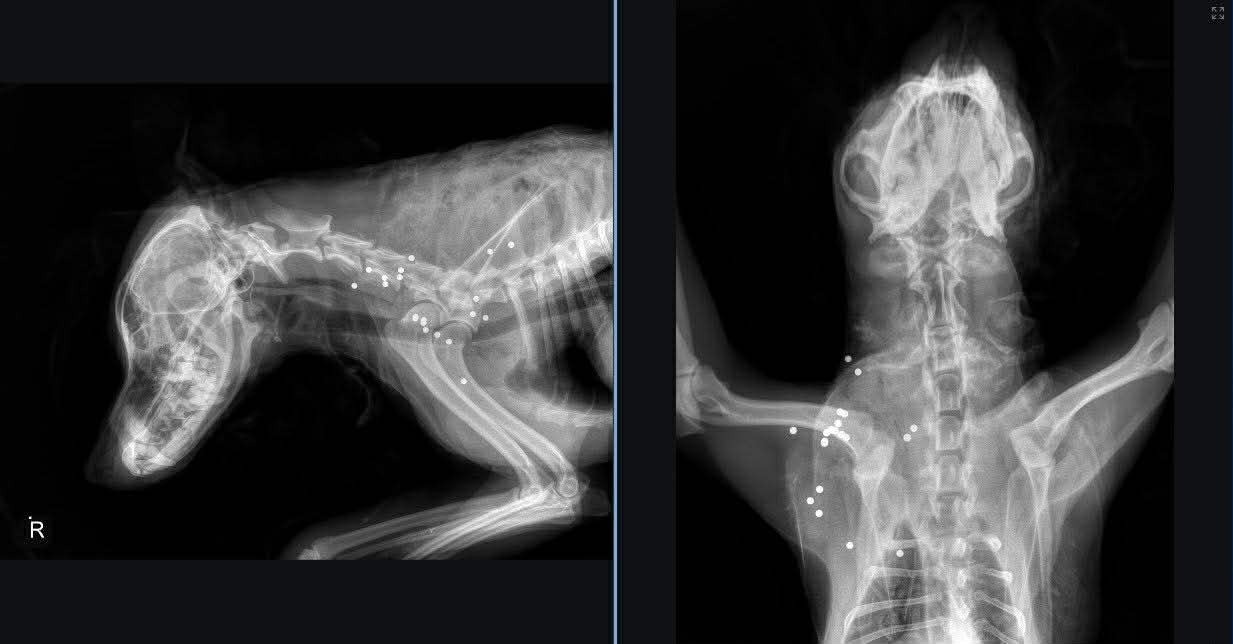

For over five hours, our volunteers shaved him and administered first aid. What they found was heartbreaking. Bailey had severe hypothermia and frostbite. His shoulder was covered in shotgun wounds, having been shot multiple times with birdshot (32 bullet holes). They cleaned and bandaged his wounds and monitored him throughout the night.

On Friday, March 6th, Bailey flew out on the first flight to Winnipeg, where he was rushed to the emergency vet. He is still there receiving the medical care he needs, including IV fluids, blood work, pain medication, antibiotics, and x-rays. He may need surgery on his shoulder but it is too soon to tell.